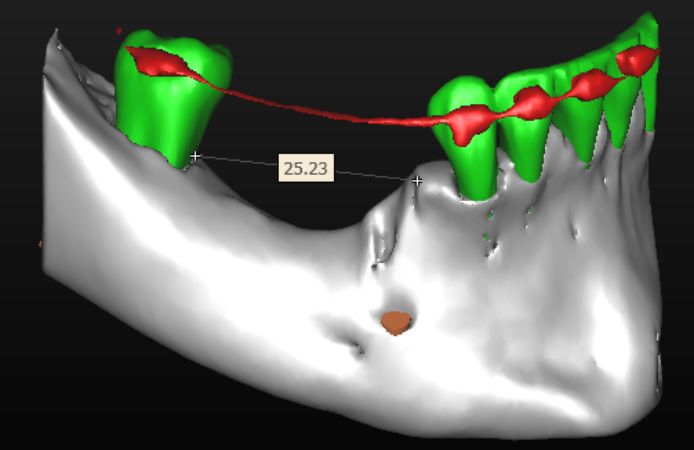

Figure 2.

CBCT evaluation showing a major bone defect in the posterior area of the mandible, with a length of 25 mm and a height of about 10 mm.